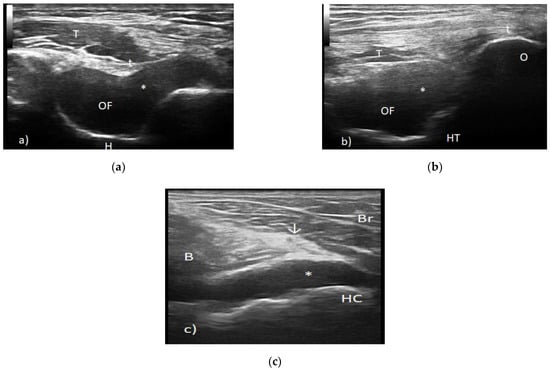

4.3. Myositis